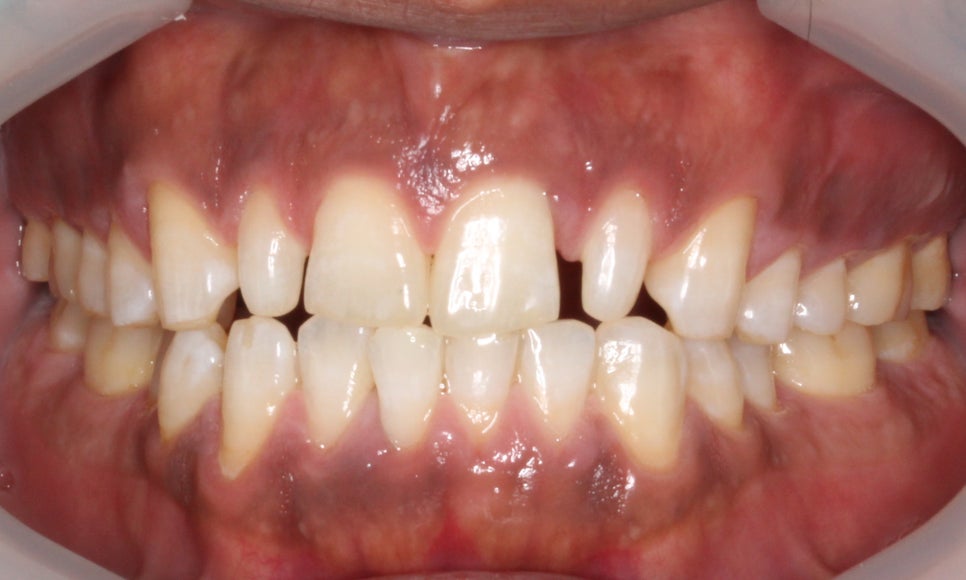

□ 앞니 벌어짐

출처:투디치과/ 앞니 벌어짐 사례의 블링스 전후 사진입니다.

전, 후 사진의 전 사진을 보시면

치아 사이가 벌어져있는 모습을 보실 수 있습니다.

블링스로 어색하지 않은 자연스러운 앞니로 개선됐네요!